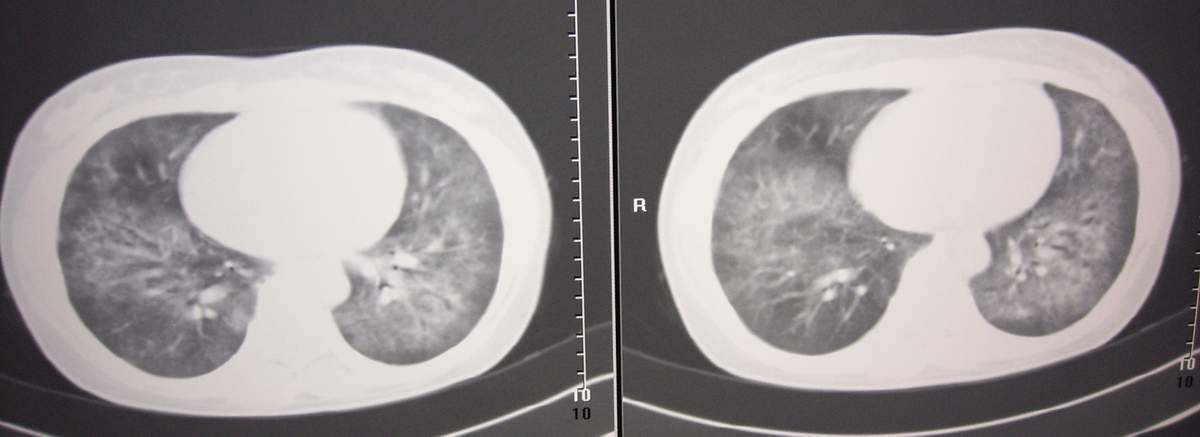

女,咳嗽、气喘2月余。

双肺纹理增多,紊乱,呈网格状,期间搀杂斑片及磨玻璃样阴影.考虑;感染性病变_首先考虑:特殊感染:嗜酸性肺病.

双肺弥漫性病变, 冠状重建肺血管增粗,建议继续上传详细临床资料,x线片

双肺弥漫磨玻璃样影,边界不清,似蝶翼征。肺纹理增多。

考虑:肺泡蛋白沉积症。建议临床进一步检查。